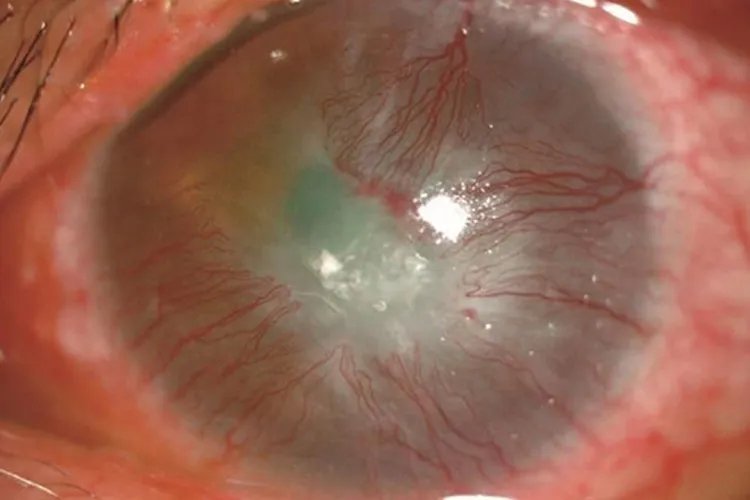

暴露性角膜炎初期角膜、结膜上皮干燥、粗糙,暴露部位结膜充血、肥厚,角膜上皮由点状糜烂逐渐融合成大片的缺损,新生血管形成。

免疫性角膜炎蚕食性角膜炎是最典型、最有代表性的免疫性角膜炎。蚕食性角膜炎病变初期,周边部角膜出现浅基质层浸润,常位于角膜内侧或外侧,随后浸润区出现角膜上皮缺损,继而形成溃疡。

浅层点状角膜炎初期症状不明显,一般见角膜上皮层出现结节状或灰色点状混沌。病因角膜炎分类不同,病因不一,感染性角膜炎由细菌感染引起,主要病原微生物为细菌、病毒、真菌和寄生虫。一些自身免疫性疾病,如类风湿关节炎可出现角膜病变。另外邻近组织的炎症可波及角膜,引发角膜炎症等。诊断根据典型的临床表现(如眼部刺激症状)及睫状充血、角膜浸润和角膜溃疡的形态特征等,角膜炎的临床诊断通常不困难,但应详细询问病史做病因诊断。治疗初期角膜炎的治疗原则是控制感染,减轻炎症反应,促进溃疡愈合和减轻瘢痕形成。细菌性角膜炎宜选用敏感的抗菌药物进行治疗。抗真菌药物仍是治疗真菌性角膜炎的重要手段,目前临床上多采用联合用药的方法以提高疗效,病情严重者可配合全身用药。单纯疱疹病毒性角膜炎可使用抗疱疹病毒药物治疗。